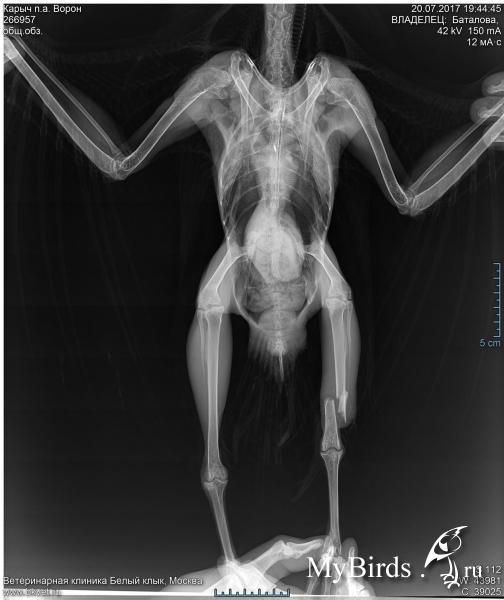

Ворон. Оскольчатый перелом голени.

В Москве 16 июля был подобран ворон. К врачу его отвезли только 20 июля.

Итак. Побывал на приёме у Томашевского.

На лапе что-то вроде лангетки. По тому, что лапа выглядит короче другой, подозреваю, что кости зафиксировали как они есть на рентгене. Надеюсь, что это не так, но пока добраться до врача не могу, не на кого оставить сороку. Да и времени уже прошло много для того, чтоб просто исправить было.

Из назначений только марфлоксин и мовалис. Ни кальция, ни витаминов для истощённой до крайности птицы со сложным переломом.

На сломанной лапе потеряна чувствительность, пальчики не реагируют, как ватные. На основании этого было заявлено, что чувствительность не восстановится и предложили подумать по поводу усыпления птицы.

Причём не было дано никакого объяснения почему потеряна чувствительность. Только категоричное заявление о невозможности восстановления без операции, но операция де слишком рискованна: может не дать результата и можно вообще потерять лапу.

Как вариант, если подтвердиться слишком высокий риск операции, буду пытаться восстановить лапу исходя из того, что есть. Лучше хромая птица, чем без ноги или мёртвая. Посему интересует, что может быть причиной потери чувствительности. Я по рентгену, кроме очевидного перелома, ничего не вижу, опыта не хватает.

На лапе 2 ложных сустава. Почему Томашевский не назначил кальций полная загадка. Через 10 дней явка, там уже будем смотреть, что делать дальше. Перелом был открытый, рана зажила хорошо.